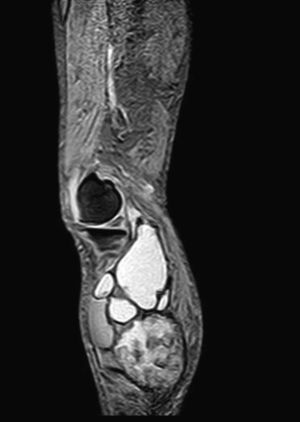

We present the case of an 83-year-old male patient with osteoarthritis, who came to the emergency room due to acute inflammation of the leg simulating DVT. On physical examination, there was a mass of elastic consistency, non-pulsatile, painful, in the popliteal fossa, extending to the leg (Fig. 1). The differential diagnosis was made with Baker cyst. The patient underwent, as a technique of choice, an ultrasound. The color Doppler mode showed patency of the deep venous system. Musculoskeletal ultrasound evidenced a well-defined collection, adjacent to the medial gastrocnemius muscle belly, full of vague echoes predominantly of low amplitude (Fig. 2) Despite being frequent, the size of the tumor made ultrasound insufficient and we decided to perform specific knee MRI with T1 potentiated sequences, T2* sequences (Figs. 3–5) and, after administration of intravenous contrast, we confirmed the existence of giant popliteal cyst of 17cm×9cm. The patient was treated conservatively, using, in the first place, nonsteroidal anti-inflammatory drugs, with clinical improvement and asymptomatic after the first 6 months. For this reason, along with the age of the patient and in spite of the cyst barely changing its size, surgical treatment has so far been dismissed.